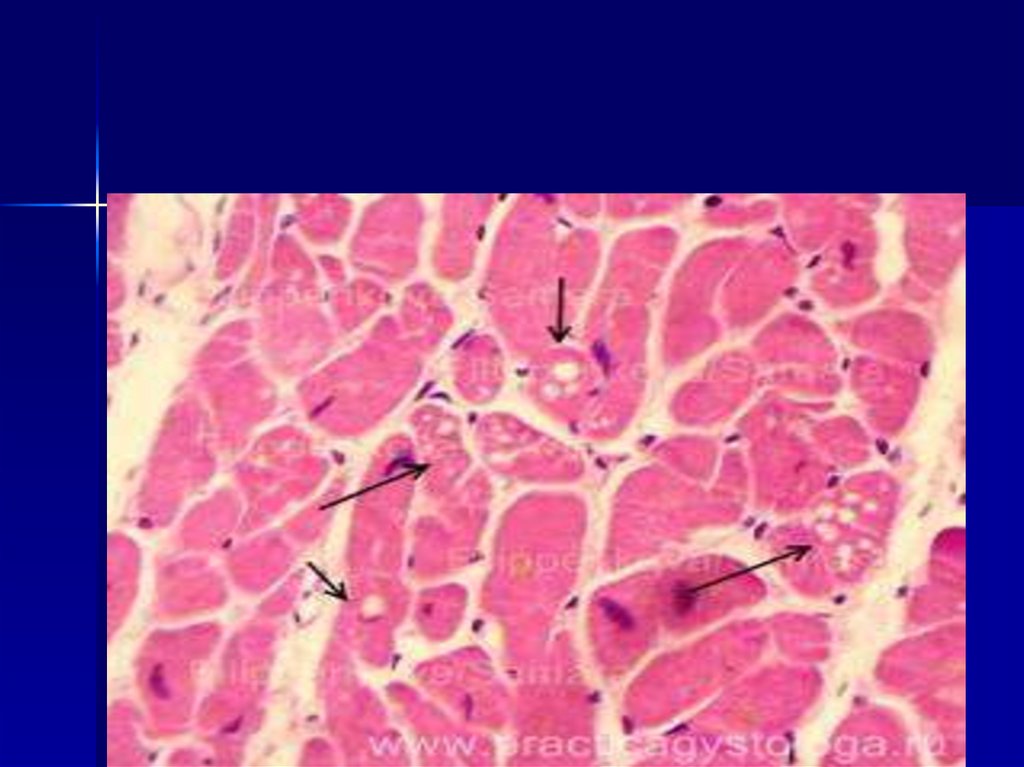

Ожирение сердца

микропрепарат

в стенке правого желудочка пролиферация лейкоцитов в строме, по

ходу сосудов миокарда, атрофия кардиомиоцитов. Окрашивание

гематоксилином и эозином